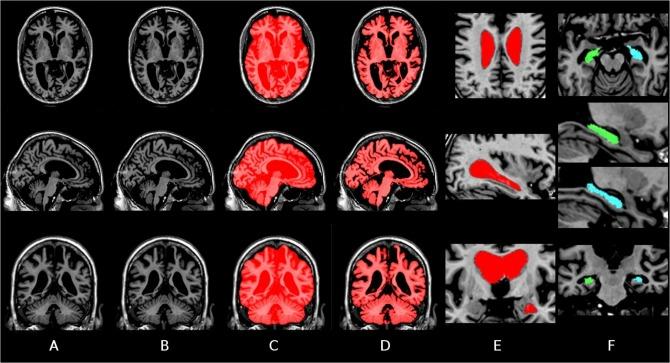

Neurodegenerative diseases such as Alzheimer's disease present subtle anatomical brain changes before the appearance of clinical symptoms. Manual structure segmentation is long and tedious and although automatic methods exist, they are often performed in a cross-sectional manner where each time-point is analyzed independently. With such analysis methods, bias, error and longitudinal noise may be introduced. Noise due to MR scanners and other physiological effects may also introduce variability in the measurement. We propose to use 4D non-linear registration with spatio-temporal regularization to correct for potential longitudinal inconsistencies in the context of structure segmentation. The major contribution of this article is the use of individual template creation with spatio-temporal regularization of the deformation fields for each subject. We validate our method with different sets of real MRI data, compare it to available longitudinal methods such as FreeSurfer, SPM12, QUARC, TBM, and KNBSI, and demonstrate that spatially local temporal regularization yields more consistent rates of change of global structures resulting in better statistical power to detect significant changes over time and between populations.